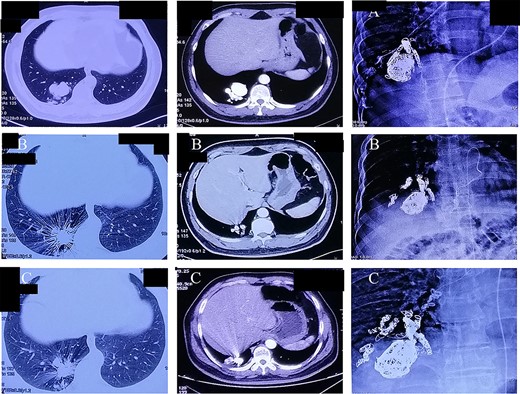

A 44-year-old man presented with hemoptysis and was diagnosed with PAVMs by computed tomography (CT) 3 years ago. In the past 2 years, the patient accepted three times right pulmonary artery branch embolization. But he appeared the same symptom and CT indicated the recurrence of PAVMs only 1 month later after each operation (Fig. 1). Not long after the third intervention, the patient was admitted to the neurology department for paroxysmal numbness and weakness of all limbs and diagnosed as TIA.

(A–C) Chest computer tomography and angiography on three times of pulmonary artery branch embolization.